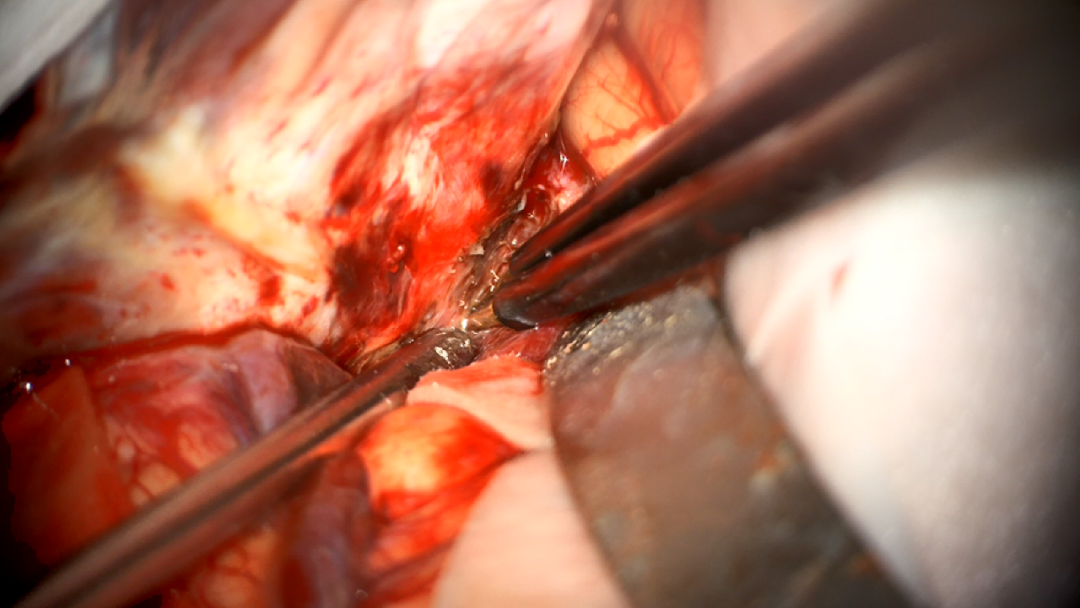

术中图片:

图8. 铣刀去除颈2-3棘突及椎板

图9. 打开硬脊膜

图10. 显露肿瘤

图11. 松解齿状韧带,进一步暴露肿瘤

图12. 分块切除肿瘤

图13. 处理肿瘤基底

14. 暴露肿瘤上极

图15. 暴露肿瘤下极

图16. 肿瘤全切

图17. 硬脊膜水密缝合